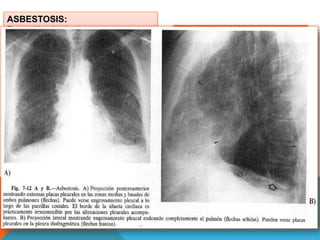

ASBESTOSIS:

Exposición al asbesto.

Inhalación de fibras de asbesto 100μ de

largo.

Minería de Asbesto y posterior proceso,

construcción de buques, textiles.

Individuos que manejan ropa

trabajadores del asbesto, viven cerca de

una mina.

HALLAZGOS RADIOLOGICOS

DE 4TIPOS:

1. Formación de Placas

2. Engrosamiento pleural difuso

3. Calcificación

4. Derrame pleural.